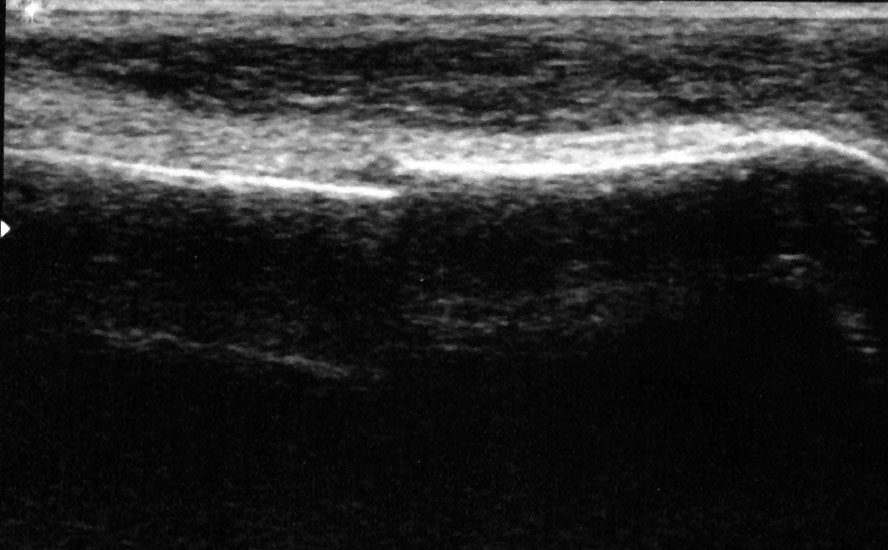

Achillessehne

Achillessehnenrupturen

Lagerung: Bauchlage, ggf. Sprunggelenk mittels Rolle unterlagert.

Schnittführung: LS über der Achillessehne, ggf. in leichter manueller Vorspannung der Achillessehne, damit diese parallel zum Schallkopf optimal eingestelt werden kann (Abb. 52).

Referenzstruktur: Direkt unter der Haut und der dünnen Subkutis liegt echogen und straff parallel die Achillessehne mit ihrem echogenen Peritendineum (Abb. 53), Tuber calcanei.

Befunde: Da die Sehne zumeist nicht glatt, sondern bündelförmig reißt, stellen sich auch in der Sonographie anders als bei den Peroneal- und Flexorensehnen keine spargelspitzenähnlichen Rissenden dar. Echogene Rissränder, umgeben von echoarmem Hämatom sind beweisend für eine Ruptur. Risse der Achillessehne können auch nur einen Teil des Sehnenquerschnitts betreffen. Daher ist die Untersuchung verschiedener TS bedeutsam (Abb. 54 bis 56). Unter Kontrolle am Monitor kann die Diagnose in maximaler Dorsalextension klarer gestellt werden (Abb. 57).